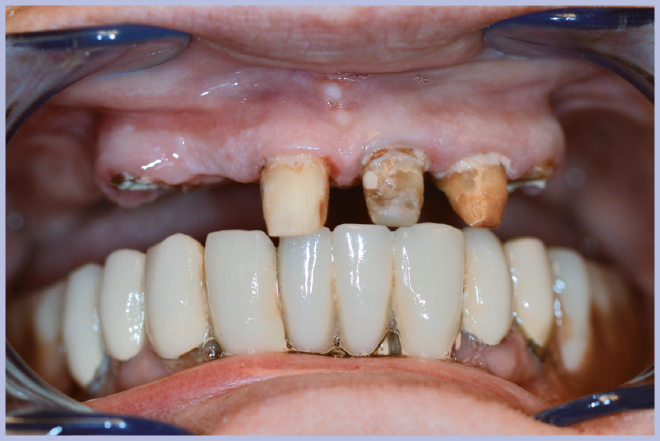

Si è presentata presso il nostro studio una paziente di 73 anni portatrice di una protesi mista (fissa e mobile) nel mascellare superiore (Fig. 1). Si è pianificata una riabilitazione immediata dell’intera arcata mediante tecnica tipo All-on-Four.

Dopo l’estrazione dei 3 elementi residui (Fig. 2), sono stati posizionati 4 impianti Max Stability Ø3,75 mm (2 di lunghezza 10 mm e 2 di lunghezza 12 mm).

- Fig. 1 – Situazione iniziale

- Fig. 2 – Elementi residui prima dell’estrazione